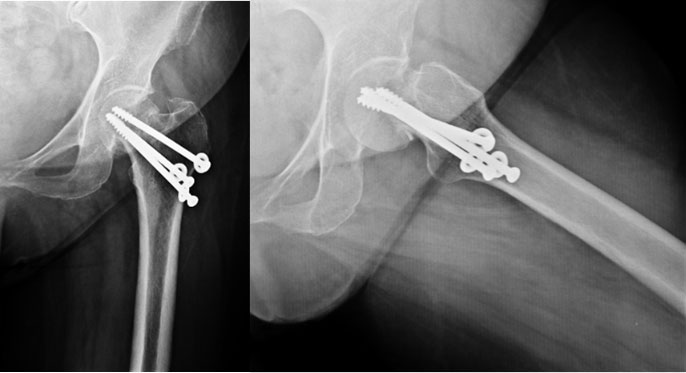

| Post Total Hip Replacement |

| The xray picture after total hip replacement. The socket (acetabular cup) was fixed with bone cement whereas the femoral stem is uncemented. The length of the limb has been restored. |